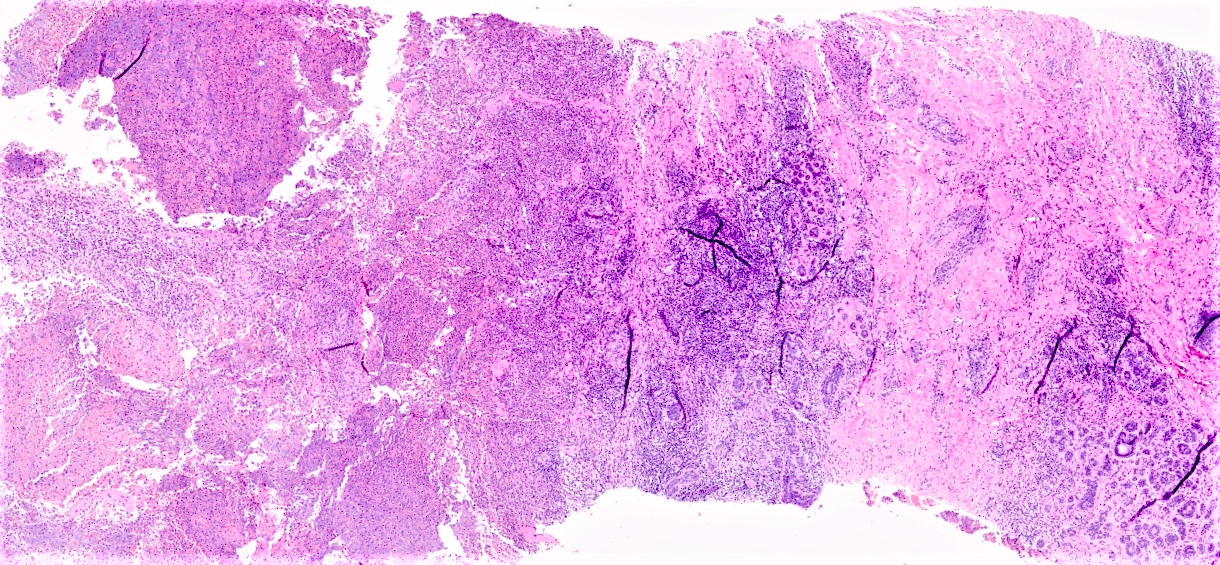

Microscopic (histologic) description

- Mixed dense inflammatory infiltrate, predominantly neutrophils, in breast tissue

- May obscure underlying normal breast tissue

- Tissue necrosis may be present

- Gram stain for microorganisms may reveal bacterial forms (gram positive cocci) associated with neutrophilic infiltrate

- Granulation tissue and chronic inflammation with resolution

- Lymphocytes, giant cells and granulomas are not typical (J Pathol Transl Med 2015;49:279)

Microscopic (histologic) images

Contributed by Kristen E. Muller, D.O.

Contributed by Ayesha Farooq, M.B.B.S. and Julie Jorns, M.D. (Case #515)